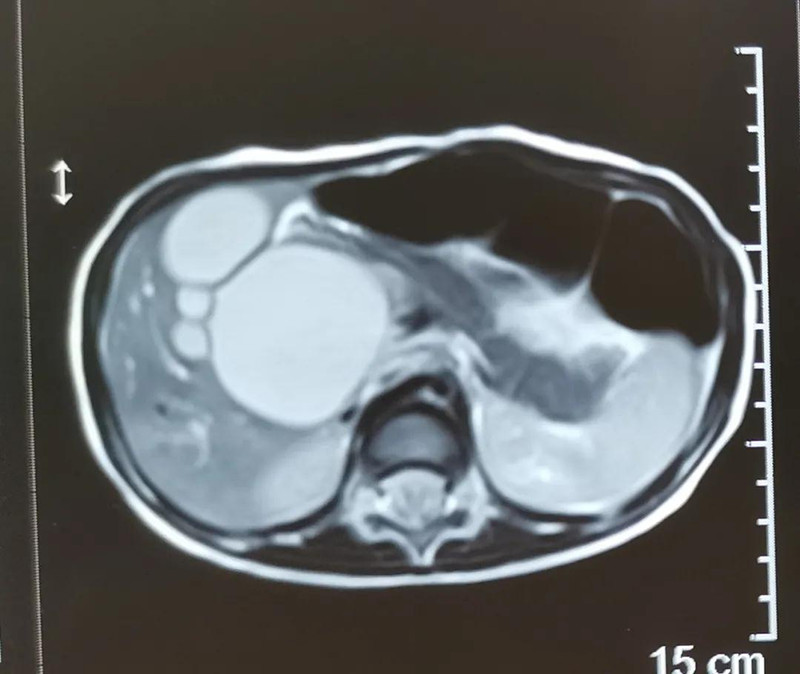

最近半个月,长春市26个月女宝馨馨(化名)脸色不好,全身发黄严重,还伴随发烧。9月23日,馨馨被家人带到啪啪网 诊治。经检查,馨馨全身发黄是因为患有黄疸,而黄疸的出现是因为胆总管发生病变,“胆总管呈现囊性扩张,下边出口被堵住,胆汁进不到肠腔里,导致孩子出现黄疸、肝功不好、白土便症状。而且胆总管胀大后,还有癌变的风险,”普外、新生儿外科主任崔钊说,馨馨需要尽快手术。为了减少损伤,崔钊主任团队制定的方案是单孔腹腔镜下胆总管囊肿根治手术。

术前准备完毕。 9月25日,馨馨进入手术室。由崔钊主任带队,按照术前设计的方案,经过8个小时的奋战,手术成功了。馨馨肝总管以下病变的胆总管及胆囊全部切除,肝总管断面与肠管吻合接上,让胆汁直接流到肠腔里,帮助消化。如术后不出现胆瘘、肠瘘,没有梗阻,馨馨以后就可以正常生活了。目前馨馨恢复得很好,黄疸渐渐缓解,肝功正常,白细胞也降下来了,排气、排便都没问题,引尿管里也没有异常东西。